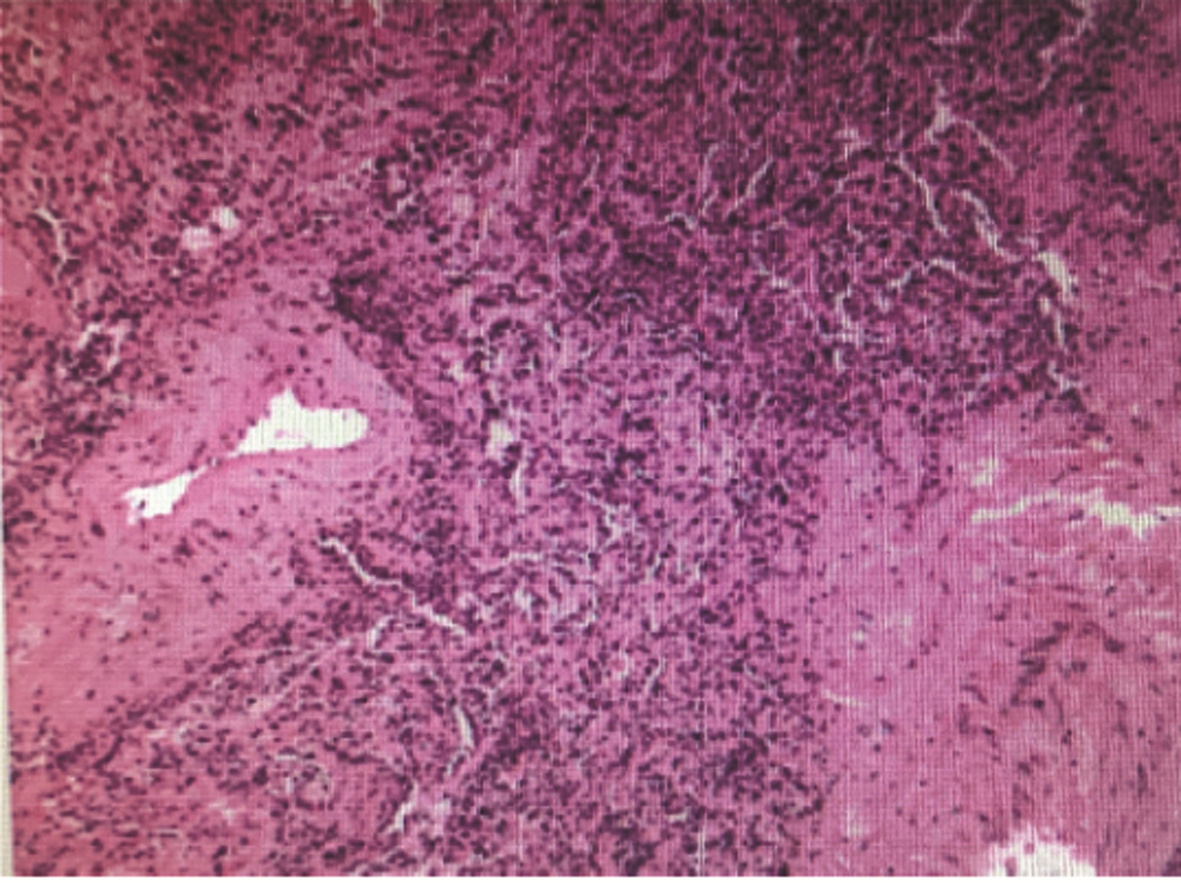

局部栓塞联合靶向免疫综合治疗肝肉瘤样癌1例报告

雷进, 张林枝, 陆荫英, 陈博文, 左石

2022, 38(4): 880-882. DOI: 10.3969/j.issn.1001-5256.2022.04.026

摘要(1323) HTML (453) PDF (3487KB)(82)

摘要: